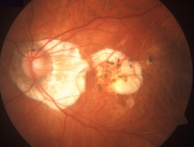

On fundus examination, the earliest manifestation is widespread pigment clumping at the level of the RPE, which is distinct from the characteristic perivascular bone-spicule pigment clumping seen in retinitis pigmentosa.[10] Subsequently, patients develop well-defined regions of atrophy with visible underlying sclera and large choroidal vessels, most commonly in the postequatorial region just outside the vascular arcades. These areas of atrophy advance centripetally and are also found in a peripapillary and parapapillary manner (See image below).[10] An island of foveal tissue may persist until later stages of the disease when central and color vision become affected from foveal atrophy. Patients have preserved larger choroidal blood vessels and normal appearing retinal vessels. In addition, choroideremia exhibits no optic atrophy, unlike the waxy pallor of optic discs seen in retinitis pigmentosa. Carrier patients can have mild RPE changes, and in severe cases, patchy RPE degeneration and areas of atrophy.[10][38] This phenotypic variability in carriers is due to lyonization in which one copy of the X chromosome is randomly silenced early in embryogenesis. Other associated ocular findings include 31% of patients developing posterior subcapsular cataracts and a small risk of macular edema or choroidal neovascularization.[39]

On fluorescein angiography, scalloped areas of missing choriocapillaris appear hypofluorescent next to brightly hyperfluorescent areas of perfused choriocapillaris (See image below). Although not a common feature, choroidal neovascularization secondary to choroideremia can develop, leading to leakage characteristic of neovascularization.[41][42][43][44][45]